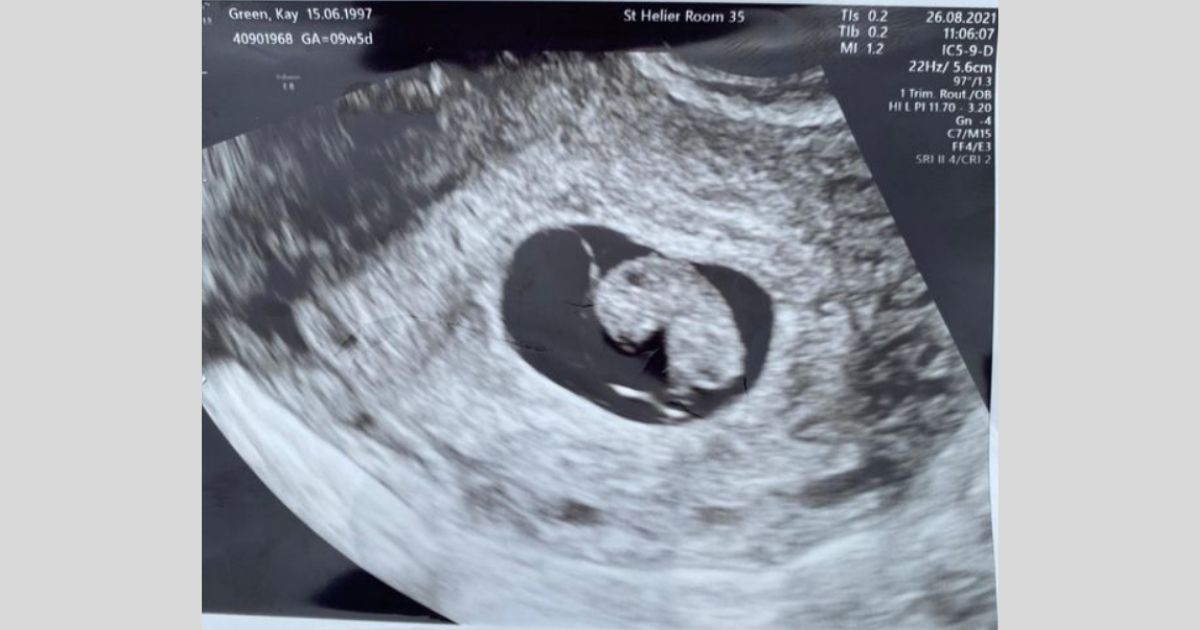

According to The Sun, Kay’s balloon had an imprinted ‘Baby Green’ on the surface. An ultrasound scan of the baby was also found inside and an attached note from the mother telling the person who finds it to contact her.